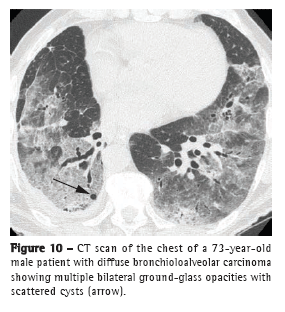

The diffuse form of BAC represents a multifocal origin, endobronchial dissemination, hematogenous metastases, or any combination of these patterns. Consolidation, nodules (Figure 9), ground-glass opacities, air bronchograms, and cysts (Figure 10), as well as peripheral distribution and distribution in the lower lobes, characterize this pattern.(20) Satellite lesions can be seen in BAC and in pneumonia.(18)